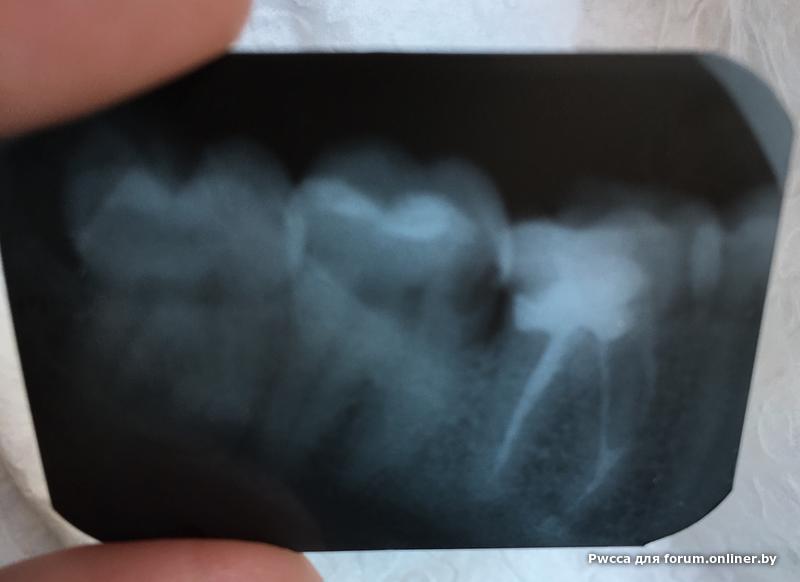

Pwcca:Ребята всем привет, подскажите позжалуйста что нужно делать с этим зубиком с утра кусочек от него отвалился , к врачу идти пока выходные не готов)

в дуге мало места, качественно не залечишь, по сему удалять.

спасать нужно 6й, а 7 тоже кариес лечить)))

Вы были полностью правы, врач сказал только удаление и нужно личить какой-то который рядом, последовательность можно выбрать, или рвать потом лечить или на оборот,

Я так хотел спасти этот зуб, но увы ваша консультация и мнение врача перевесили.